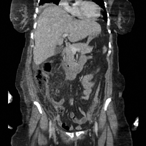

Stone fragments migration into subcapsular renal hematoma post flexible ureterorenoscopy (unique presentation)

Ahmed Nazer and others

Journal of Surgical Case Reports, Volume 2019, Issue 5, May 2019, rjz125, https://doi.org/10.1093/jscr/rjz125